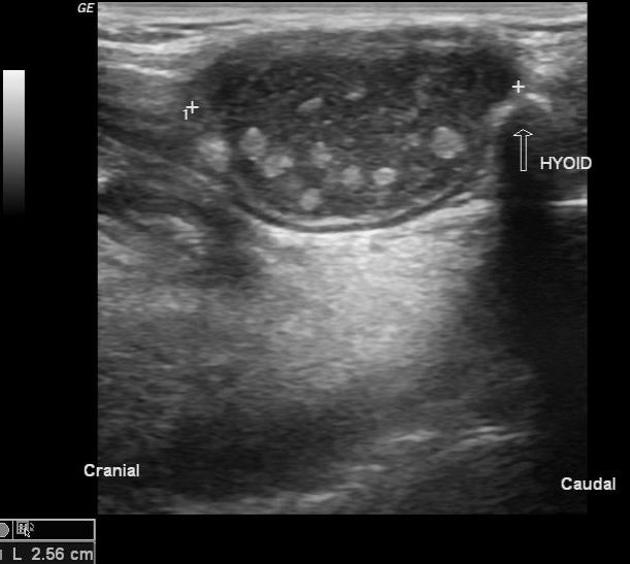

From www.dr-karazaitri-ma.net

Pathologie Cervicale échographie Dr KARAZAITRI M.A Kyste Du Cuir Chevelu Echographie Il s’agit d’une tumeur bénigne qui se développe sous la peau du. un kyste du cuir chevelu est une formation bénigne arrondie qui se développe sous la peau, résultant généralement du blocage des glandes sébacées ou. Dérivé de l’épithélium infundibulaire •. kyste pilaire, kyste sébacé, kyste trichilemmal, et même loupe sont autant de noms qui désignent les kystes. Kyste Du Cuir Chevelu Echographie.